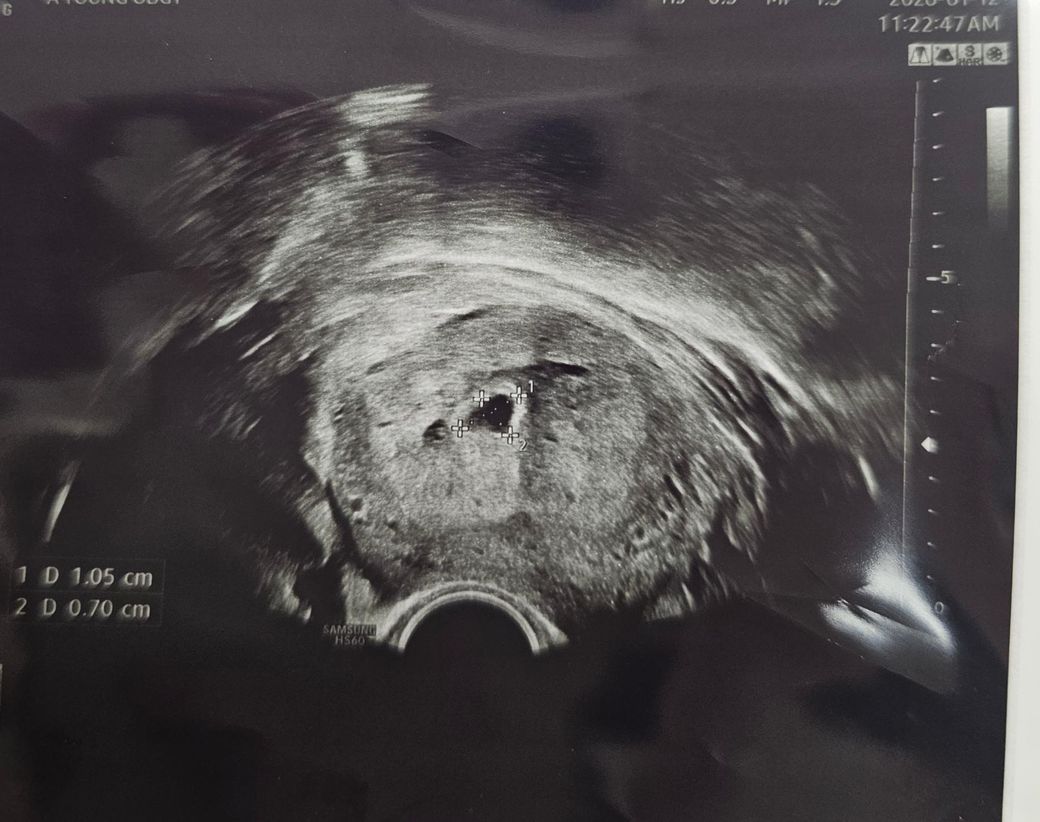

초음파를 봤는데 배테기로 했을때 배란일 기준 +21일차로 5주 극초반이었을텐데 아기집이 9mm조금 안되는 크기입니다. 생리주기는 좀 긴편이라 막생 후 3주뒤 배란이 됏을 거로 추정됩니다..

같은 시기에 비해 아기집은 크고 그에 비해 난황은 안보이는데 아기집이 8mm~10mm 정도가 되면 난황이 보이는게 보편적인지?.. 아직까지는 정상범위로 걱정을 안해도되는 수준인건지? 저때 난황이 안보이면 예후가 안좋은건지?.. 아기집이 먼저 커지고 이후 난황과 속도가 맞아질수 있는건지? 어느정도까지 기다려볼만한지 모든게 걱정스럽고 궁금합니다..😭 다음주에 보고 유산생각도 하라고 하셔서..아기집보자마자 유산이야기듣고 심란하네요ㅠ

• 1번 째 사진